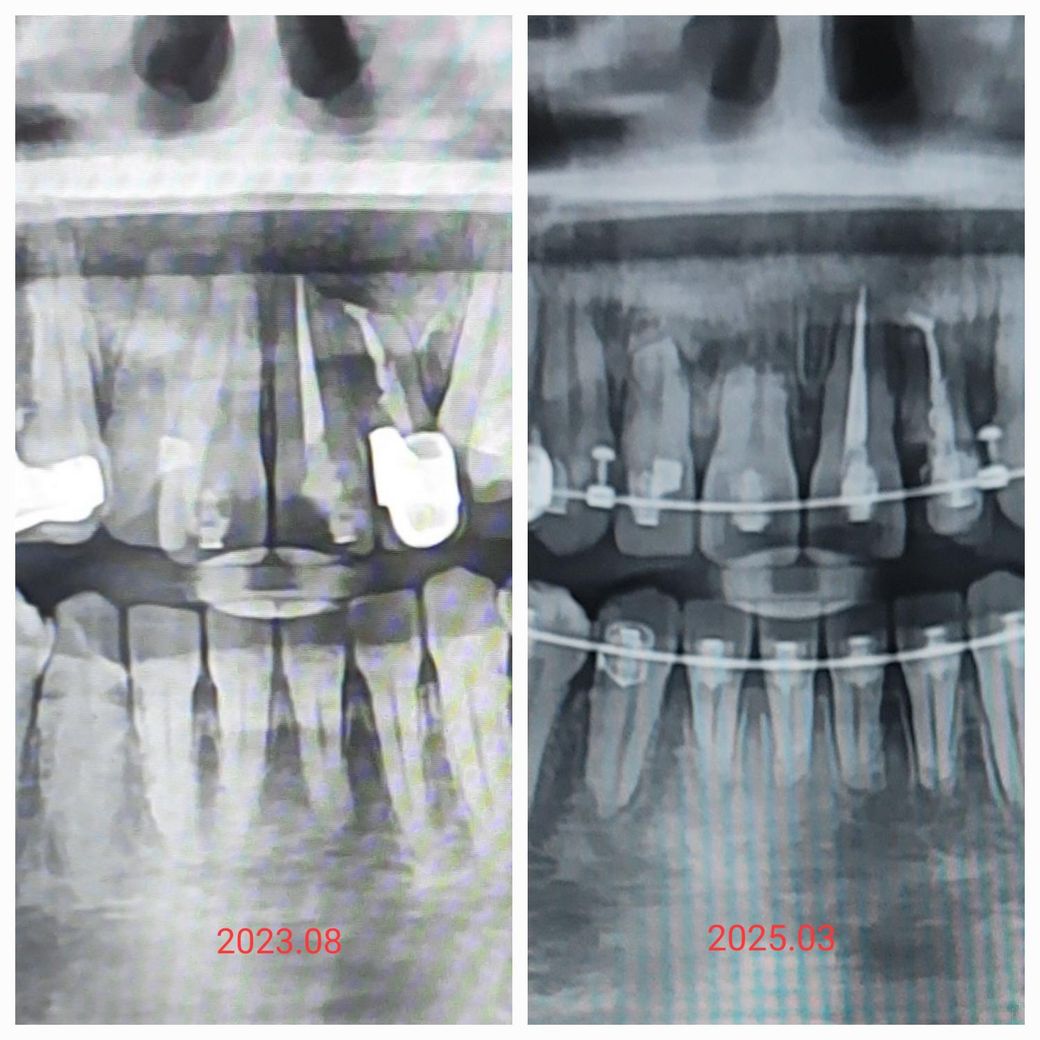

교정중 치근흡수된 위에 앞니 4개치아주변 잇몸에 염증이 심하게 있는건가요? ( 똑같은 질문 올렸었는데 사진첨부를 깜빡하여 다시 올립니다)

23년 6월말에 치근단낭종으로 뼈가 많이 녹아있었고 낭종수술하고 한달 뒤에 교정시작했고요

24년12월에 사진찍었었는데 그때는 뿌리가 이렇게 많이 녹았다는걸 못 느꼈는데

이번달에 찍은 사진보니 좀 이상해서 교정전 사진이랑 비교하니

앞니가 3분의1은 없어진 것 같아요

원래 3개월만에 이렇게 빠르게 치근흡수가 진행되기도 하는건지

아니면 제가 낭종있던거 때문에 염증이 재발하며 옆으로 퍼진건지..

아랫니도 치근흡수 됐는데 윗니랑 끝부분 모양새가 달라서 윗니에 큰 문제가 생긴것 같아서 불안합니다 ㅠ

나종제거를 하고나서 치근흡수가 진행이 됩니다. 거기에 교정을 하다보니 치아 뿌리 흡수가 더 빨리 진행된거 같습니다.

상악에 있는 치아는 2년전과는 크게 다른것이 보이지는 않습니다. 파노라마 사진의 경우 찍는 각도에 따라서 치아의 길이가 다르게 보일수 있습니다.

아래 앞니 치아의 경우에는 치근 흡수가 이루어 진것으로 보입니다.

치근단낭종으로 뼈가 많이 녹아있었던 것으로 인해 치근이 흡수되었을 것으로 생각됩니다.

아닙니다. 윗니 수술 직후 사진은 낭종 제거한 부위가 검게 보인 것이며, 25년 3월 사진은 낭종 수술 부위 뼈가 차서 주변과 같은 색으로 보이기 때문인 것으로 보입니다. 낭종 제거시 치아뿌리 끝부위 잘라내는 치근단절제술 같이 한 것으로 치아뿌리끝 부위가 검게 보입니다.